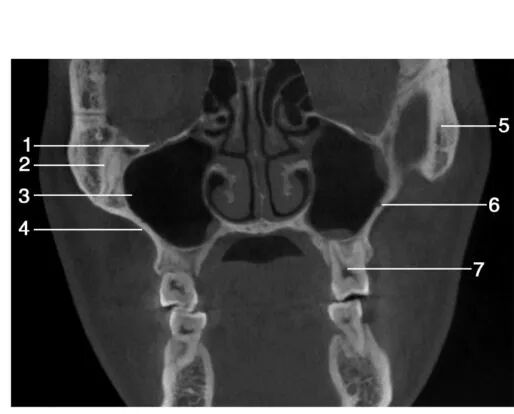

1.眶下裂( inferior orbital fissure) ; 2.眶下神经管( canal for infraorbital nerve) ; 3.上颌窦( maxillary sinus) ; 4.上颌窦前壁(anterior wall of maxillary sinus) ; 5.上颌第一磨牙( maxillary first molar) ; 6.眶底( floor of orbit) ; 7.上颌窦后壁( posterior wall of maxillary sinus) ; 8.翼突( pterygoid process) ; 9.上颌第三磨牙( maxillary third molar) ; 10.上颌第二磨牙( maxillary second molar)